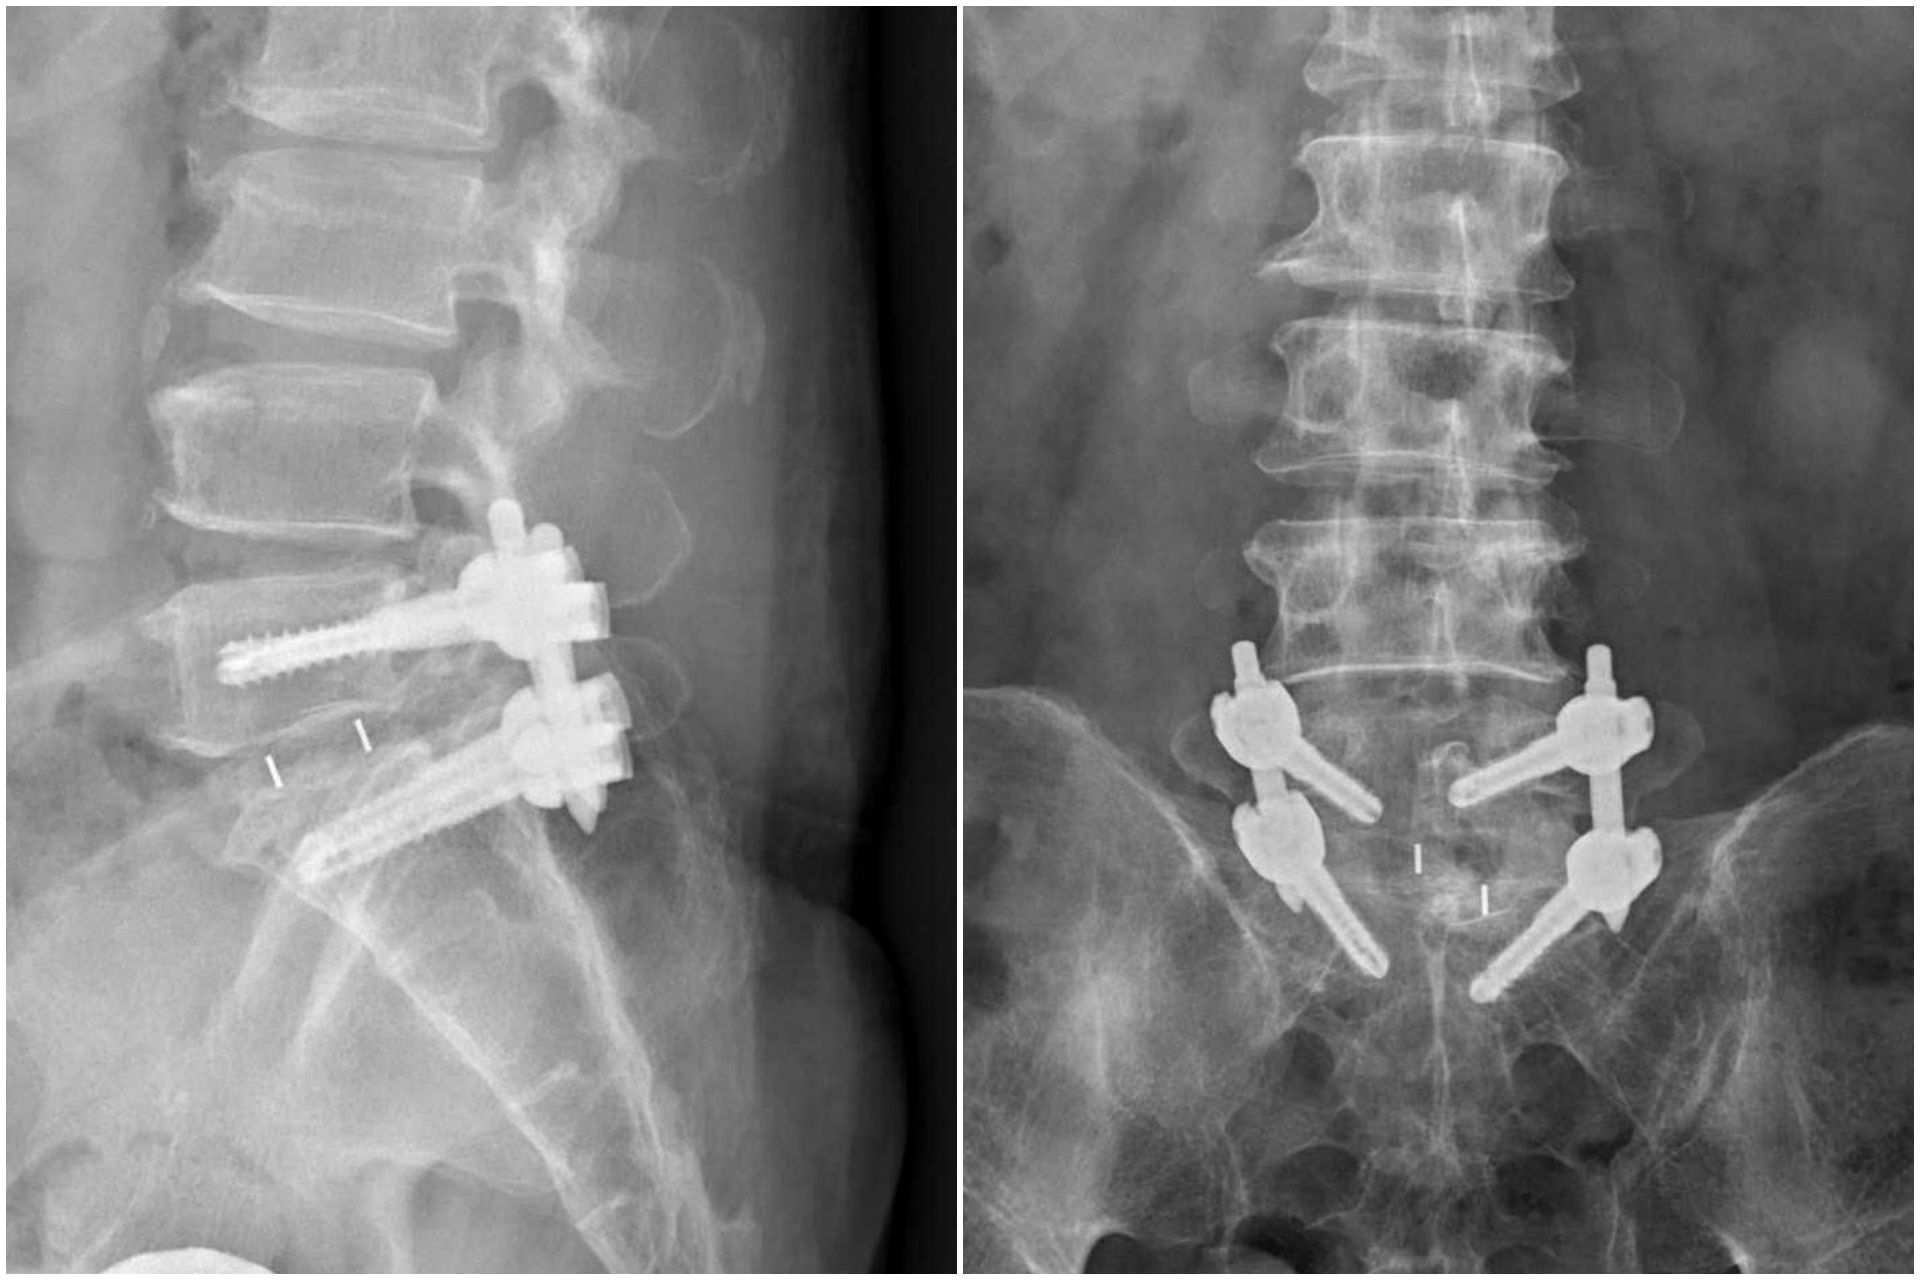

影像檢查顯示,張先生的第五節腰椎椎弓骨折合併脊椎解離。洪祥益主任表示,這類病人多半表現為腰痠背痛、久坐久站困難,通常可先藥物治療觀察,但相較於其他類似問題的病人,張先生疼痛異常明顯,手術中發現脊椎關節內長滿痛風石,這些痛風石如白色黏稠物般,附著在神經與關節縫隙間,若不清乾淨,就會持續引發神經發炎與疼痛,甚至比坐骨神經痛更強烈。團隊透過顯微鏡,在不傷及神經的情況下,仔細將痛風石刮除清理,再以微創固定融合手術完成治療。